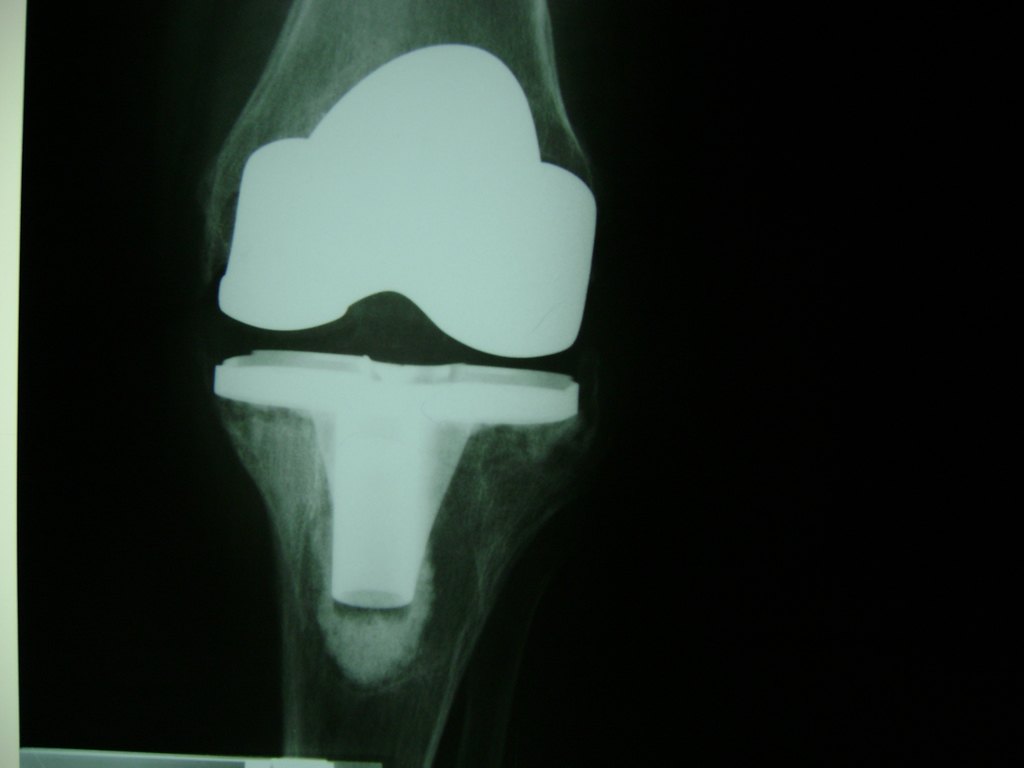

La artroscopia de rodilla es un cirugía en el cual la estructura interna de la articulación es examinada ya sea para realizar un diagnostico o para realizar un tratamiento, este procedimiento se realiza utilizando un instrumento parecido a un pequeño tubo llamado artroscopio.